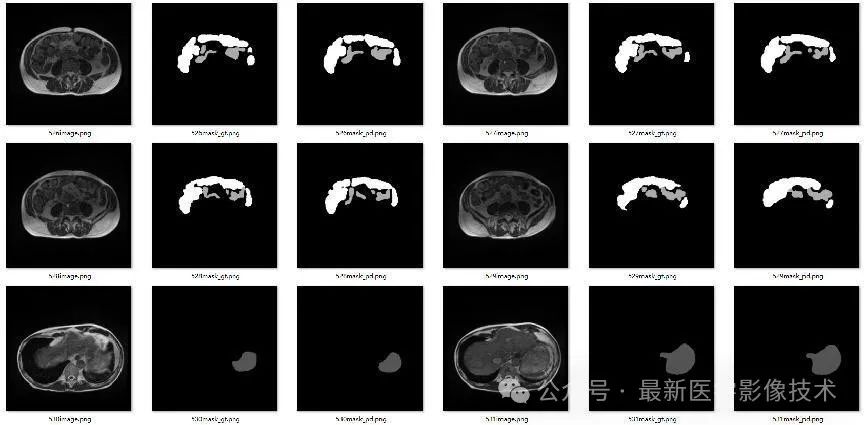

4、验证集部分分割结果